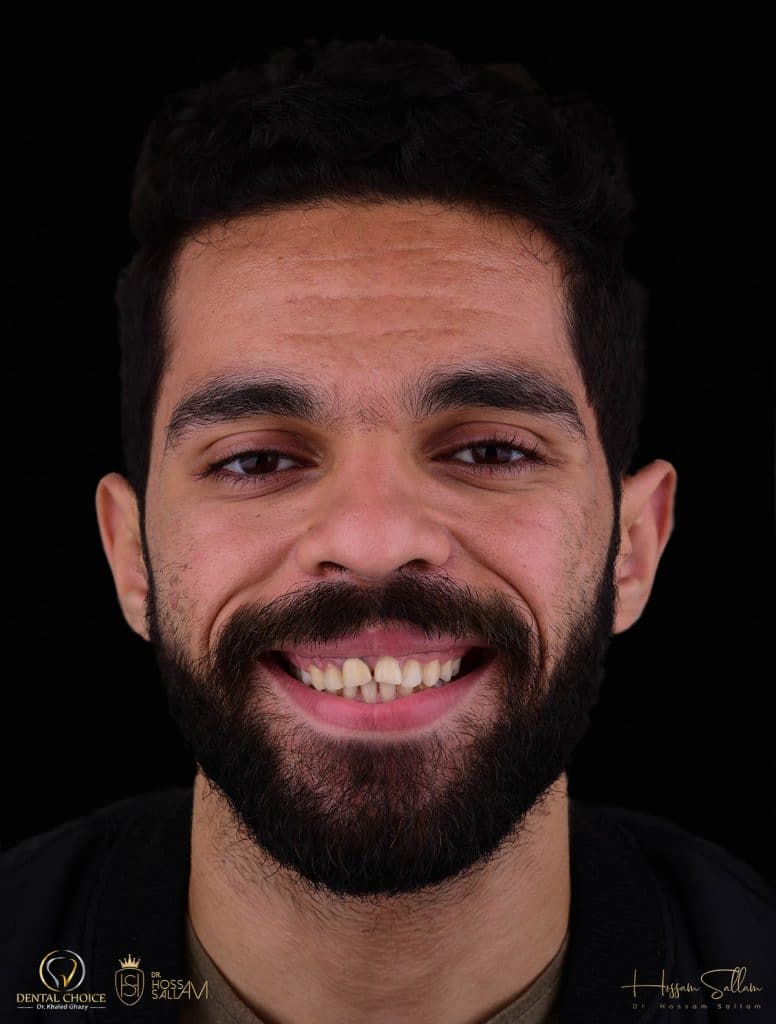

pre operative situation

This pic showing

- Reverse Smile line

- black shadow at buccal corridor region

- in accurate teeth ratio

- gum Smile specially at posterior region

- inadequate zenith position